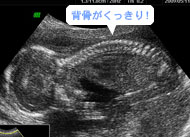

首からお尻まで、背骨の骨のひとつひとつが、しっかり映っています。(妊娠18週)

骨や筋肉が発達して羊水の中で活発に、自由に體(tǐ)を動かします。